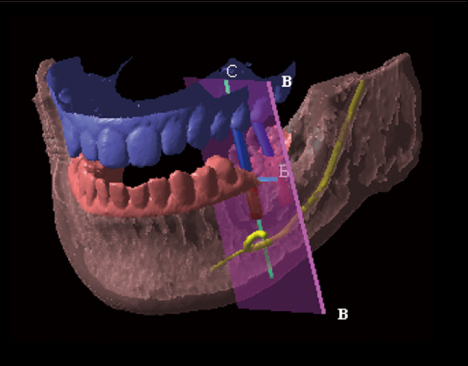

インプラント

歯科インプラントとは、失った歯の部分にチタン製の人工歯根(インプラント)を埋め入れて、歯本来の機能や見た目を取り戻す治療方法のことをいいます。 失った歯の部分を治療しますので、周囲の歯に負担をかけることがありません。 また、これまでにあった歯と同じような役割を果たしますので、噛む力を分散させ、残っている自分の歯を守ることにもなります。